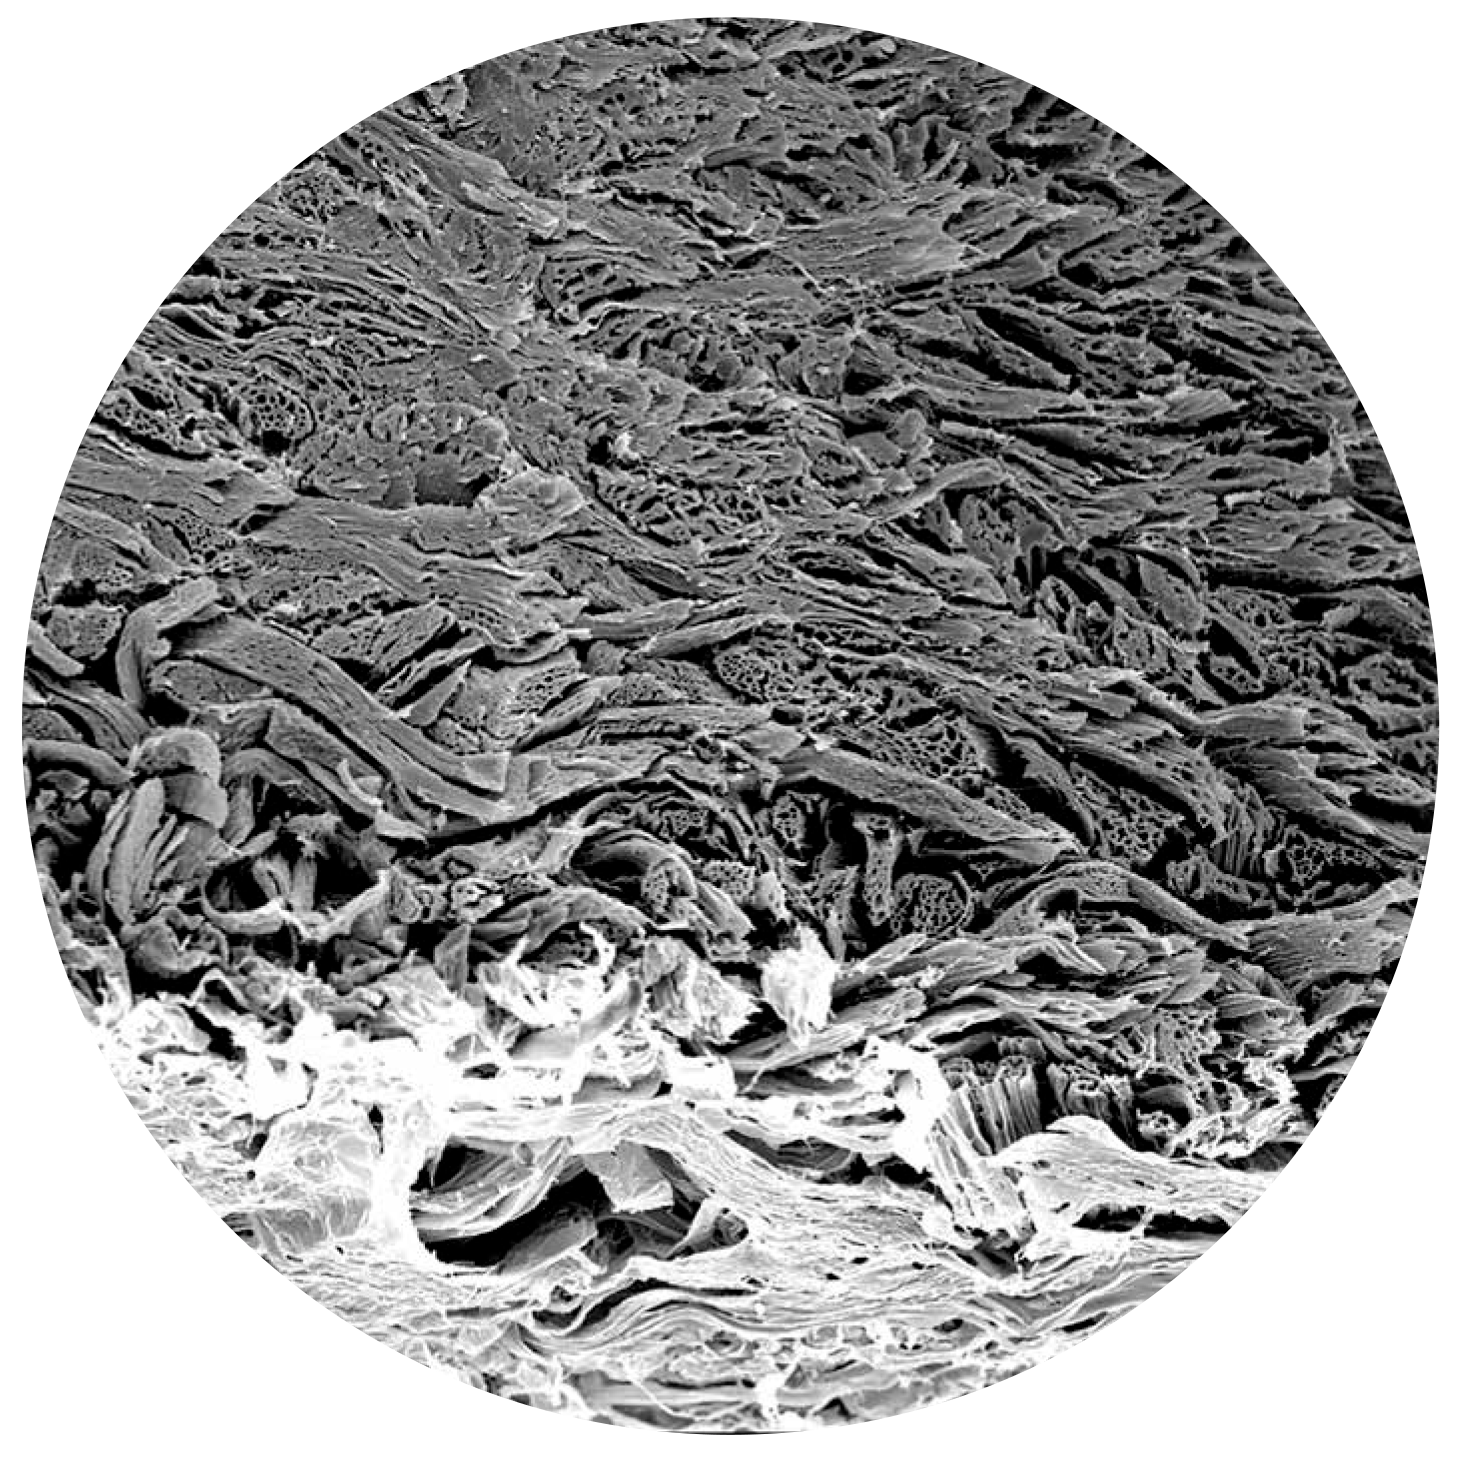

Microstructure (SEM)

The homogeneous and porous collagen microstructure of biocade® supports cell migration and tissue integration.